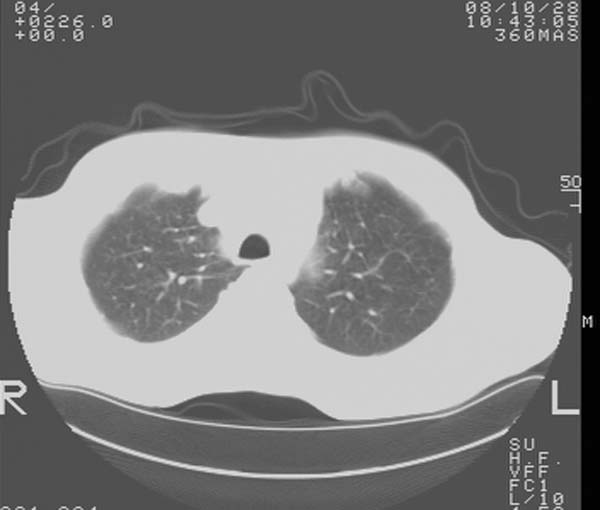

m,65y。半年前发现颈小结节,逐渐增多增大,现双侧耳后、颌下及颈部表浅淋巴肿大。胸片示双肺门增大。外院曾穿刺诊断为淋巴结核。在我科作胸腹部ct,我们觉得外院病检有误。现将图像上传请战友讨论。

纵隔内及腹膜后广泛淋巴结肿大,脾大,肝内似可见低密度影,结合病史半年前发现颈小结节,逐渐增多增大,现双侧耳后、颌下及颈部表浅淋巴肿大。考虑淋巴瘤。

纵隔,双肺门腹膜后多发淋巴结重大,非融合,肝脾轻度肿大,双肺野弥漫性小结节;考虑淋巴瘤,结节病可能性

纵隔内,双肺门、腋窝及腹膜后多发肿大淋巴结影,肺内小结节影,肝脾体积增大,支持淋巴瘤。肝内多发低密度影,考虑小囊肿。